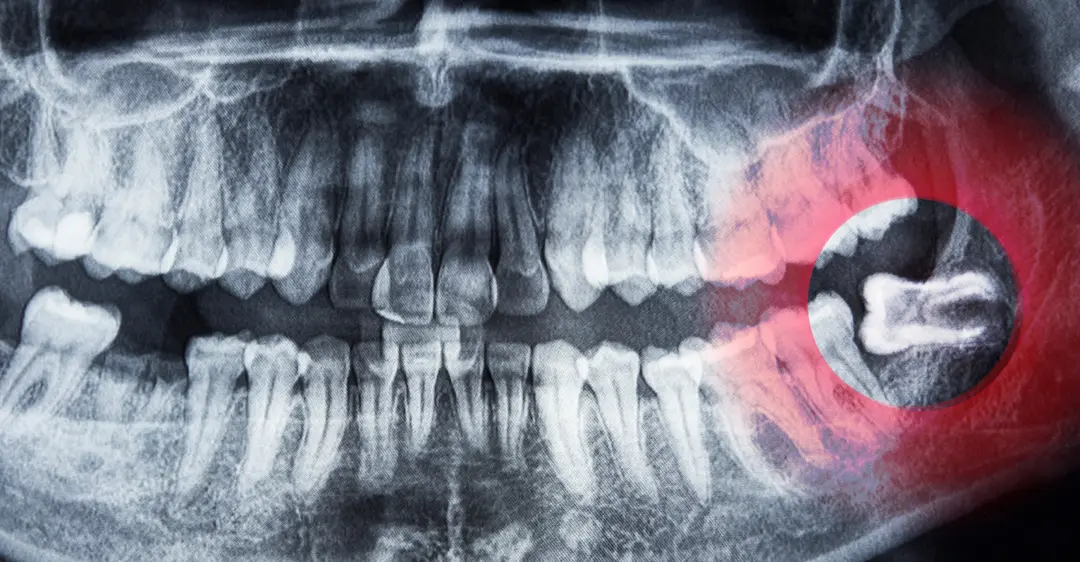

Impacted Wisdom Teeth

When a wisdom tooth is not able to erupt and take its appropriate position in your mouth, it is considered impacted, a common but potentially serious issue that stems from a lack of space for these molars. This problem can occur in different degrees, as the molars can be:

- Partially impacted

- Completely impacted

- Soft tissue impacted, which means the tooth erupts through the jawbone tissues but is not able to break through the gums

Impacted teeth can lead to discomfort, infection, and crowding. This issue can also stop you from practicing the appropriate oral hygiene, and it can lead to damaged neighboring molars as well as possible cyst formation around the wisdom tooth!